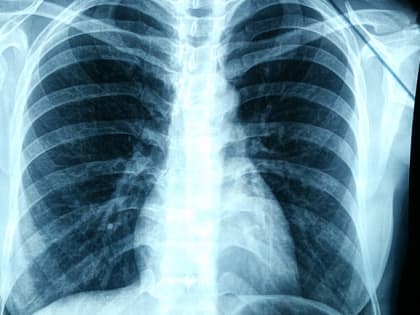

«Поймать» рак. Почему стоит бросить курить и быть внимательным к своим легким

Заведующий отделением торакальной онкологии Архангельского клинического онкодиспансера, хирург Андрей Мармуро рассказал, какие заболевания помог выявить COVID-19, с каким кашлем нужно обращаться к врачу,